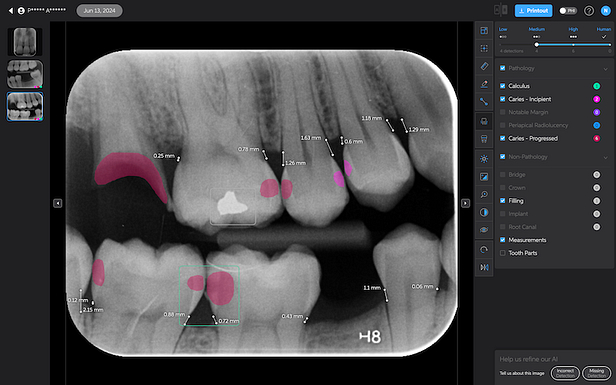

Pearl’s Second Opinion can report on six conditions on 2D x-rays at this stage. Let's go over each one of the AI detections below:

Bone Measurements

The system provides automated measurements from the crest of the bone to the cementoenamel junction (CEJ). These measurements are color-coded to indicate severity:

- White: 0-2.5 mm

- Yellow: 2.5-4 mm

- Amber: >4 mm

This feature is helpful for periodontal assessments, streamlining the process of identifying areas of bone loss. However, it's important to note that image angulation can affect the accuracy of these measurements, a limitation the system acknowledges.

I found these lines to be incredibly useful when describing patients' periodontal health. Cool feature, no doubt.

Calculus Detection

Green squares highlight areas of radiographic calculus. This tool is useful for hygienists and dentists in treatment planning and patient education.

Notable Margins

Purple squares indicate areas of notable margins, such as potential overhangs or open margins on existing restorations.

Caries Detection

The best for last and arguably the most well-thought-out feature. Especially with the tooth segmentation mode, which makes it easier for patients to understand their diagnosis and treatment plans.

The system uses two shades of pink to indicate potential caries:

- Light pink: Incipient caries (100% in enamel) - we will often review

- Darker magenta: Caries extending into dentin - we need to restore

The system even provides a percentage breakdown of enamel vs. dentin involvement. I have been blown away by its accuracy while using it, and it makes something that feels quite subjective (reading shades of grey) into a science.

Other features of Second Opinion

One of the strengths of Second Opinion's AI detection system is its flexibility. You can toggle different types of detections on and off, allowing for customized views depending on the focus of examination or patient education needs.